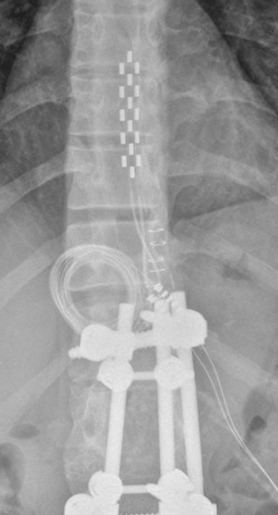

Phase de test avec une électrode chirurgicale pour soulager des douleurs chroniques post-chirurgicales

Electrode per-cutanée visant à soulager des douleurs chroniques post-chirurgicales